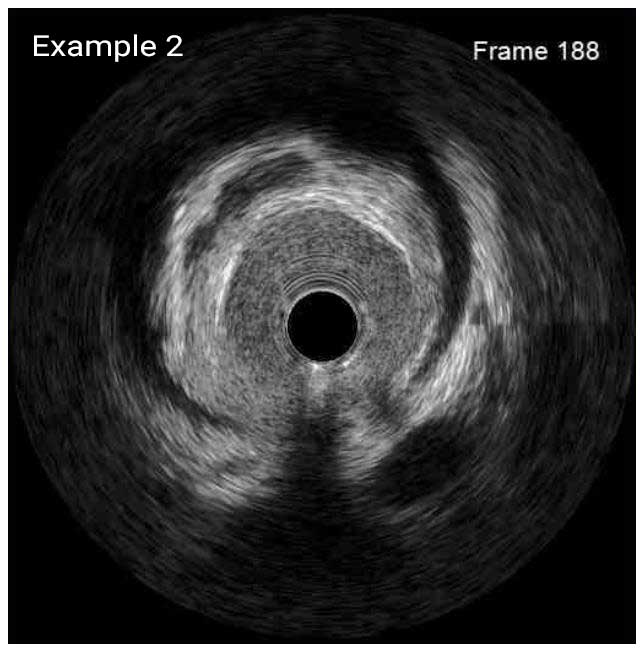

In a normal coronary artery, an ultrasound reflection is generated at two tissue interfaces: at the border between blood and the leading edge of intima and at the external elastic membrane (EEM) located at the media-adventitia border. The resulting three-layered structure consists of the tunica intima (bright, relatively echogenic layer compared to lumen and media), media (dark, less echogenic layer compared to intima) and adventitia (bright). Tunica media has lower ultrasound reflectance due to lower content of collagen and elastin (highly reflective materials) compared to intima and adventitia. The trailing edge of the intima, internal elastic membrane (IEM), cannot always be distinguished clearly on IVUS images. Similarly, IVUS cannot detect the outer border of adventitia due to comparable echoreflectivity of adventitia and periadventitial tissue.1,2